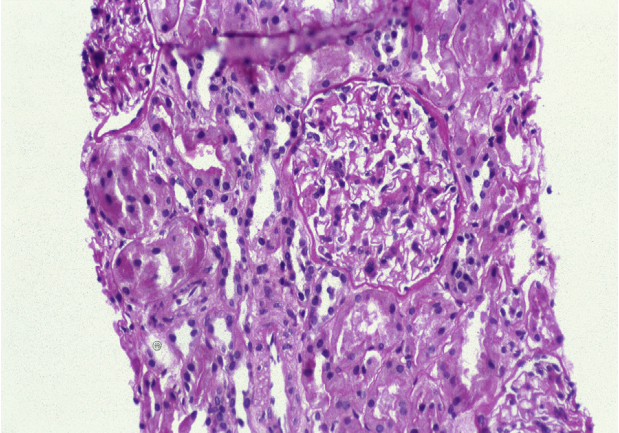

狼疮型肾炎Ⅳ型(弥漫性LN),腊肠状毛细血管壁沉积,外轮廓光滑,提示内皮下沉积,散在的小颗粒状毛细血管壁沉积,可能是上皮下沉积,偶有系膜沉积(免疫荧光,IgG)。

狼疮型肾炎Ⅴ型(膜性LN),弥漫性颗粒状沿着毛细血管环和系膜区染色(免疫荧光,IgG)。

狼疮型肾炎Ⅴ型(膜性LN),弥漫性颗粒状沿着毛细血管环和系膜区染色(免疫荧光,IgG)。